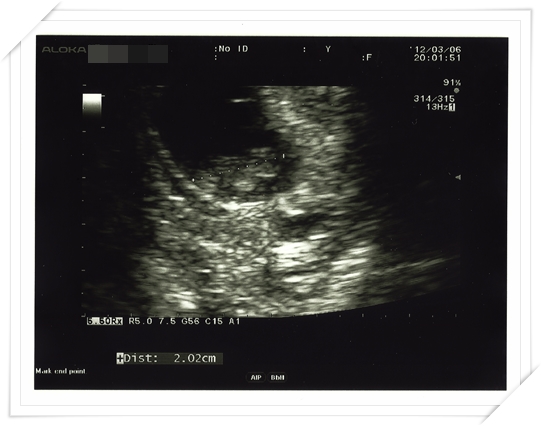

然後這天產檢

醫生一幫我照超音波 就跟我說 Baby 長得很好唷!

長大很多呢!

上一次照 才0.6公分

今天已經大到 他光是照 還沒拿游標量 就知道長大好多囉!

接著拿游標量 居然已經兩公分啦!!!!!

真是令人振奮的消息 看來在日本餐餐吃魚的高蛋白飲食 有長到baby 身上啦 (我自認~~~

)不過照完了超音波

醫生就覺得 以baby 的大小來看 應該不是本來我們自己推算的七週左右

而應該是早了一週 變成八週半左右才對

醫生告訴我 如果baby 下次來 還是長的這麼快

那應該就只是 我們的baby 營養特別好 長得比較好而已

醫生也不會再改變預產期囉~~~~

所以忽然就這樣咻~~~~地一下 我忽然被推進了一整個星期